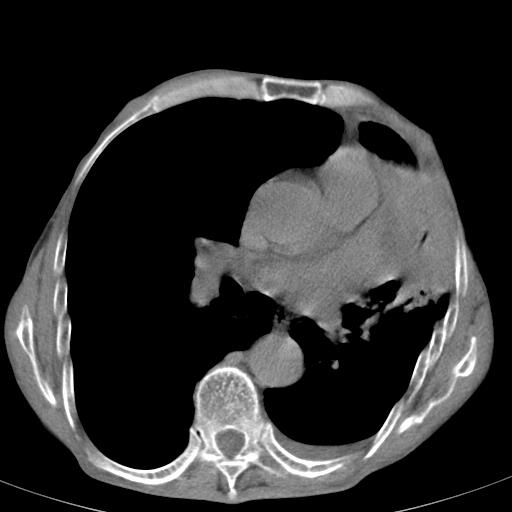

患者78岁,咳嗽胸闷一年余,近月来左侧胸痛;

患者左侧胸廓塌陷说明是长期病变,考虑tb性胸膜炎可能性大,另外有明显的肺气肿,建议行结核菌素实验,或者增强扫描

1.慢支肺气肿。2.左肺感染,建议治疗后复查。3.左侧少量胸水。

1.慢支肺气肿。2.左肺感染,建议治疗后复查,待除外继发性肺结核合并感染。3.左侧少量胸水。

1)考虑左肺慢性感染性病变(结核可能)。2)左肺上叶周围型肺癌不排除;建议追踪复查。3)肺气肿。4)左侧胸腔积液,左侧胸膜增厚、粘连。